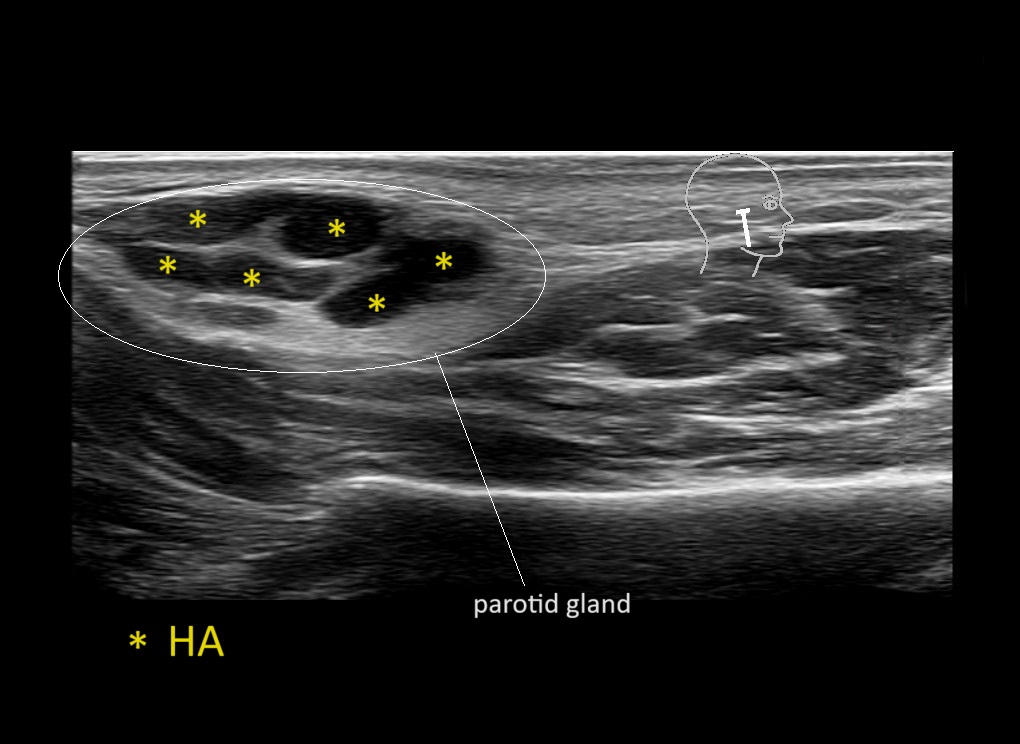

Filler injections in the parotid gland may go unnoticed, however, inflammatory reactions and abscesses may occur. Hypervascularity can be seen with color doppler. Filler deposits are supposed to be injected into the superficial fatty layer . The space to inject into this layer may be limited. Routinely we measure a width of 2-4 millimeters with sometimes subcutaneous layers being less than one millimeter thick.

Study the first image to recognize the different layers. If you are sure about the layers, swipe to the second image to view the answer (if applicable).